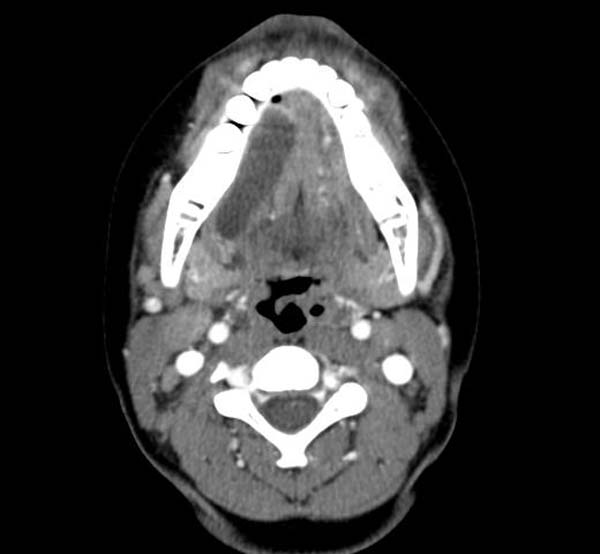

КТ-изображения опухолей корня языка